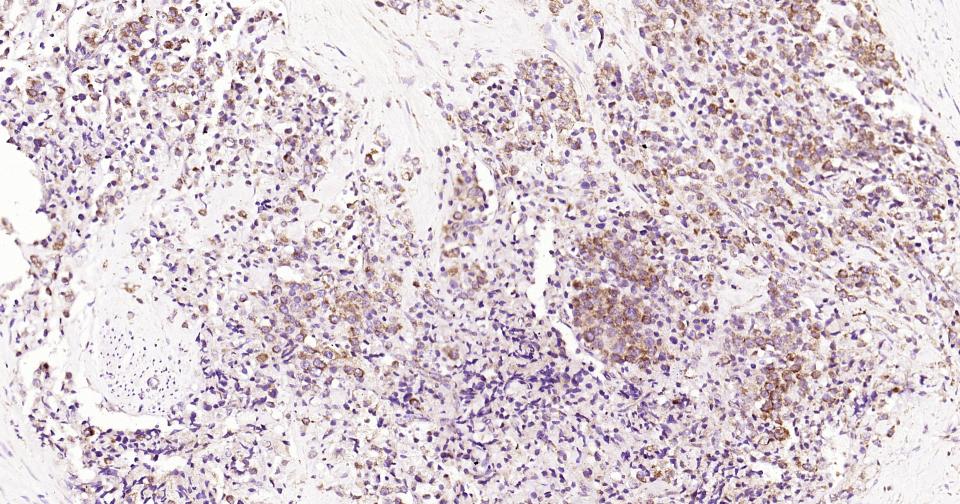

Paraformaldehyde-fixed, paraffin embedded Human Prostate Tumor; Antigen retrieval by boiling in sodium citrate buffer (pH6.0) for 15 min; Antibody incubation with PIK3C3 Monoclonal Antibody, Unconjugated(bsm-61161R) at 1:200 overnight at 4°C, followed by conjugation to the SP Kit (Rabbit, SP-0023) and DAB (C-0010) staining.